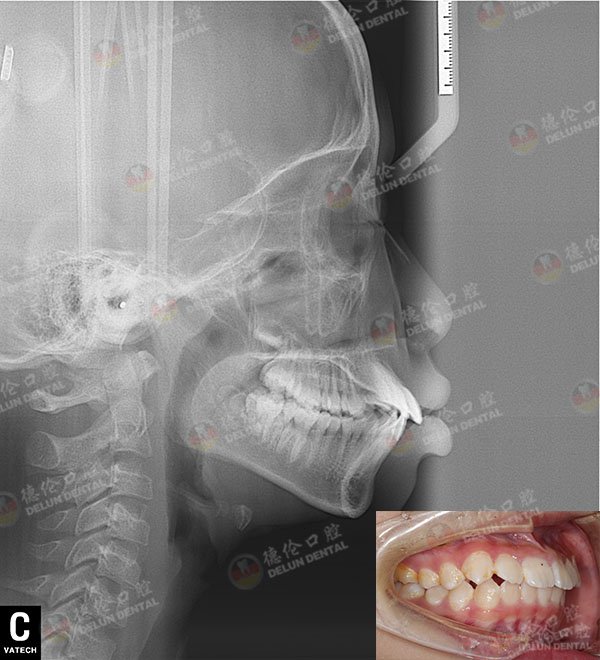

牙齿症状:上颌牙前突,牙列不齐

治疗方案:半隐形陶瓷托槽矫正

年幼时,一口整齐的乳牙,忽闪闪的大眼睛,秀气的五官都让沁曦显得十分可爱。但是随着年纪增长,沁曦替换出的恒牙显得不尽人意。从一口整齐的乳牙,到齿列不齐,前牙外突,这对沁曦产生了很大的负面影响。

矫正前口内侧面照

这一下,沁曦的牙齿矫正就可以经过德伦团队的会诊以及方案制定,能够程度上保证矫牙舒适度与完成度。本身沁曦就正处于发育的高峰期,是一个非常有利与矫正的时期。考虑到沁曦本人作为一个孩子的敏感,以及面对镜头的需要,德伦专家一致决定为沁曦做半隐形陶瓷托槽矫正。